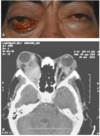

Dx

Celulitis orbitaria